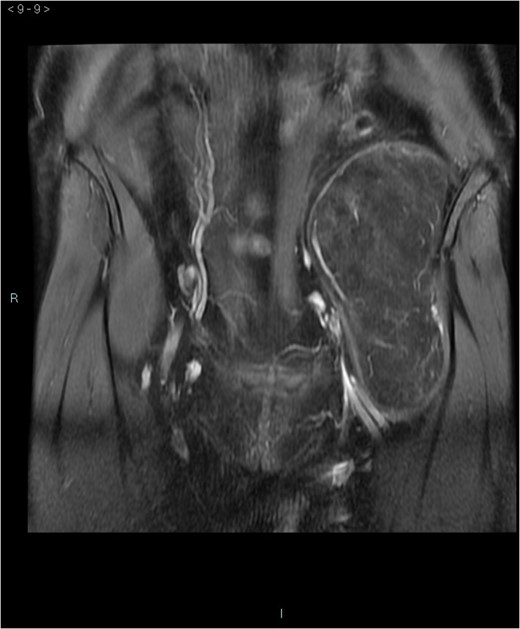

A 58-year-old woman was evaluated for lower abdominal pain, without additional symptoms. An abdominal ultrasonography revealed the presence of a 15 cm homogenous mass, located in the left pelvic cavity. Subsequent MRI showed a capsulated mass, isointense with the adipose tissue, longitudinally extending from the left inguinal area to the left leg root and located on the medial aspect of the left iliac bone. MRI also revealed within the mass some fibrotic branches containing small blood vessels. No evidence of extracapsular invasion of the surrounding structures was evident (Figs 1–6).

After multidisciplinary team discussion, surgical resection of the mass was planned: through a Pfannestiel incision a retroperitoneal dissection was performed, until exposition of the overmentioned mass, which was completely enucleated. During the operation, the absence of tumor infiltration of the surrounding structures was confirmed. No intraoperative histopathologic examination was carried out and the lesion was sent for definitive pathological examination. Macroscopically, the tumor presented as a well circumscribed encapsulated soft mass without infiltrative growth and/or satellite nodules. Tumor size was 15 × 7.5 × 6.5 cm3 and the weight was 309 g. External surface was smooth and the section had a lobulated aspect with a yellow-brown color. The histopathology examination revealed an adipocyte proliferation with moderate volume variation. Two populations of adipocytes were identified: one cluster with small, bland nuclei and the other with round to oval nuclei, with vacuolated eosinophil cytoplasm. In addition, rare multinucleated giant cells were observed. No cellular atypia was present. Immunohistochemistry was positive for S-100 and negative for MDM-2 (murine double-minute type 2) (Figs 7–9). Postoperative course was uneventful and the patient was discharged after 2 days.

Preoperative differential diagnosis is mainly based on radiologic imaging and is very difficult, because no pathognomonic signs exists for diagnosis of hibernoma; usually CT-scan shows an homogenous lesion, whose density is between subcutaneous fat and skeletal muscle; MRI shows slightly lower signal intensity on T1 weighted spin-echo (T1WSE), marked enhancement and partial fat suppression on short Tau inversion recovery (STIR) and fat-saturated sequences [5].